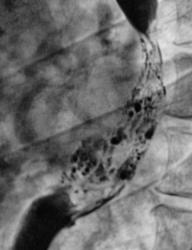

По представленным снимкам, у меня сложилось впечатление что пищевод как бы сдавлен извне (овал), возможно образованием в заднем средостении; при этом на довольно продолжительном участке есть нарушение архитектоники складок слизистой с множественными участками barium depletion (стрелки), свидетельствующими в пользу изъязвления.

Выводы: изначально хотелось бы узнать анамнез и жалобы; но так как их не представлены, буду рассуждать опираясь только на семиотику. У меня 2 варианта: опухоль пищевода с преимущественно интра-муральным ростом или образование средостения с прямой инвазией пищевода вплоть до слизистой оболочки, в данном случае может быть много вариантов. Моя рекомендация-конечно КТ, посмотреть стенки пищевода и окружающие структуры.

А по поводу представленного случая, мне кажется слизистая прослеживается на всём протяжении, местами депо-бария, однако ближе к ретрокардиальному сегменту некоторые сомнения есть. На первом месте думаю что лейомиома( часто главным осложнением является кровотечение), а 2ом образование средостения.

Коллега v1tal: "А по поводу представленного случая, мне кажется слизистая прослеживается на всём протяжении, местами депо-бария, однако ближе к ретрокардиальному сегменту некоторые сомнения есть. На первом месте думаю что лейомиома (часто главным осложнением является кровотечение), а 2 ом образование средостения".

Соглашусь коллегой v1tal, картина достаточно характерна для лейомиомы пищевода( посмотрите книгу Тагера "Рентгенодиагностика заболеваний пищевода").Да и клиника подтверждает это. Кончно, КТ прояснит ситуацию ( dr.Mario прав, если есть возможность сразу сделать КТ, в подобной ситуации. то R-скопия пищевода не нужна, но всё зависит от доступности КТ, для большинства больниц России пока это роскошь). Эндоскописты не нашли изменений т.к. образование подслизистое ( они его не видят).

Коллеги! Может я и назойливо повторяюсь, но в плане заключения по данному случаю, мы пока не имеем право чётко судить, зло- здесь или добро, а может это и болезнь Крона (хотя такое эндоскописты должны были бы увидеть). Пока есть признаки объёмного образования, и кстати не доказано пока (рентгенологически) что изначально этот объём исходит именно из пищевода. Депо бария (barium depletions спасибо за перевод v1tal!) на некоторых участках есть; и нарушение архитектоники слизистой в некоторых участках тоже есть. Так как эндоскопия не дала результата, и если предположить что имеем дело с лейомиомой, то большая вероятность того, что биопсия окажется негативной, так как не всегда биопсийные шипцы могут "пробить" слизистую и дойти до более глубоких слоев стенки. Поэтому, я всё равно полагаю что в данном случае показано КТ исследование.

Исходя из вышесказанного, по данному случаю: сдавление просвета и смещение пищевода мягкотканным образованием, выходяшим за пределы стенки, изъязвление передней стенки пищевода. Заключение: подслизистая опухоль пищевода с изъязвлением, вероятнее всего лейомиома. Рекомендации: эндоУЗИ с биопсией, КТ.

После проведенного рентгенологического исследования органов грудной полости - рентгенографии и томографии, при которой были выявлены увеличенные лимфатические узлы в корнях лёгких и средостении, было проведено рентгенотелевидение пищевода с прицельной рентгенографией и исследованием пищевода на трохоскопе, с контрастированием пищевода водной взвесью сернокислого бария "различной консистенции" - от сверхжидкого - до пастообразного, для "выяснения состояния" заднего средостения. Была зарегистрирована и документирована "локальная деформация пищевода" на протяжении 9,5 см. с перестройкой структуры "рельфа слизистой оболочки".